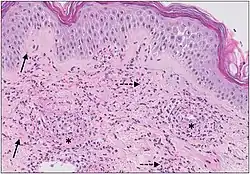

The small vessels in the skin affected are located in the superficial dermis and include arterioles (small arteries carrying blood to capillaries), capillaries, and venules (small veins receiving blood from capillaries).[5] In general, immune complexes deposit in vessel walls leading to activation of the complement system. C3a and C5a, proteins produced from the complement system, attract neutrophils to the vessels.[9] Once activated, neutrophils then release preformed substances, including enzymes, causing damage to vessel tissue.[9] Evidence of this process can be seen with a sample of removed skin tissue, or biopsy, viewed under a microscope. Neutrophils are seen surrounding blood vessels and their debris within vessel walls, causing fibrinoid necrosis. This finding on histological examination is termed "leukocytoclastic vasculitis".[5]